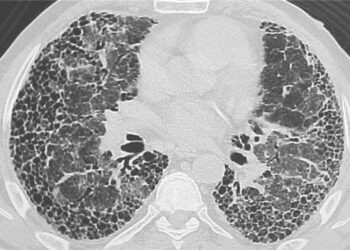

Akciğer Sertleşmesi İçin Yeni Bir İlaç

INCREASE kısa adlı randomize-kontrollü faz 3 çalışmasında interstisyel akciğer hastalığı (akciğer sertleşmesi) ve akciğer hipertansiyonu olan hastalarda solunum yoluyla uygulanan ...